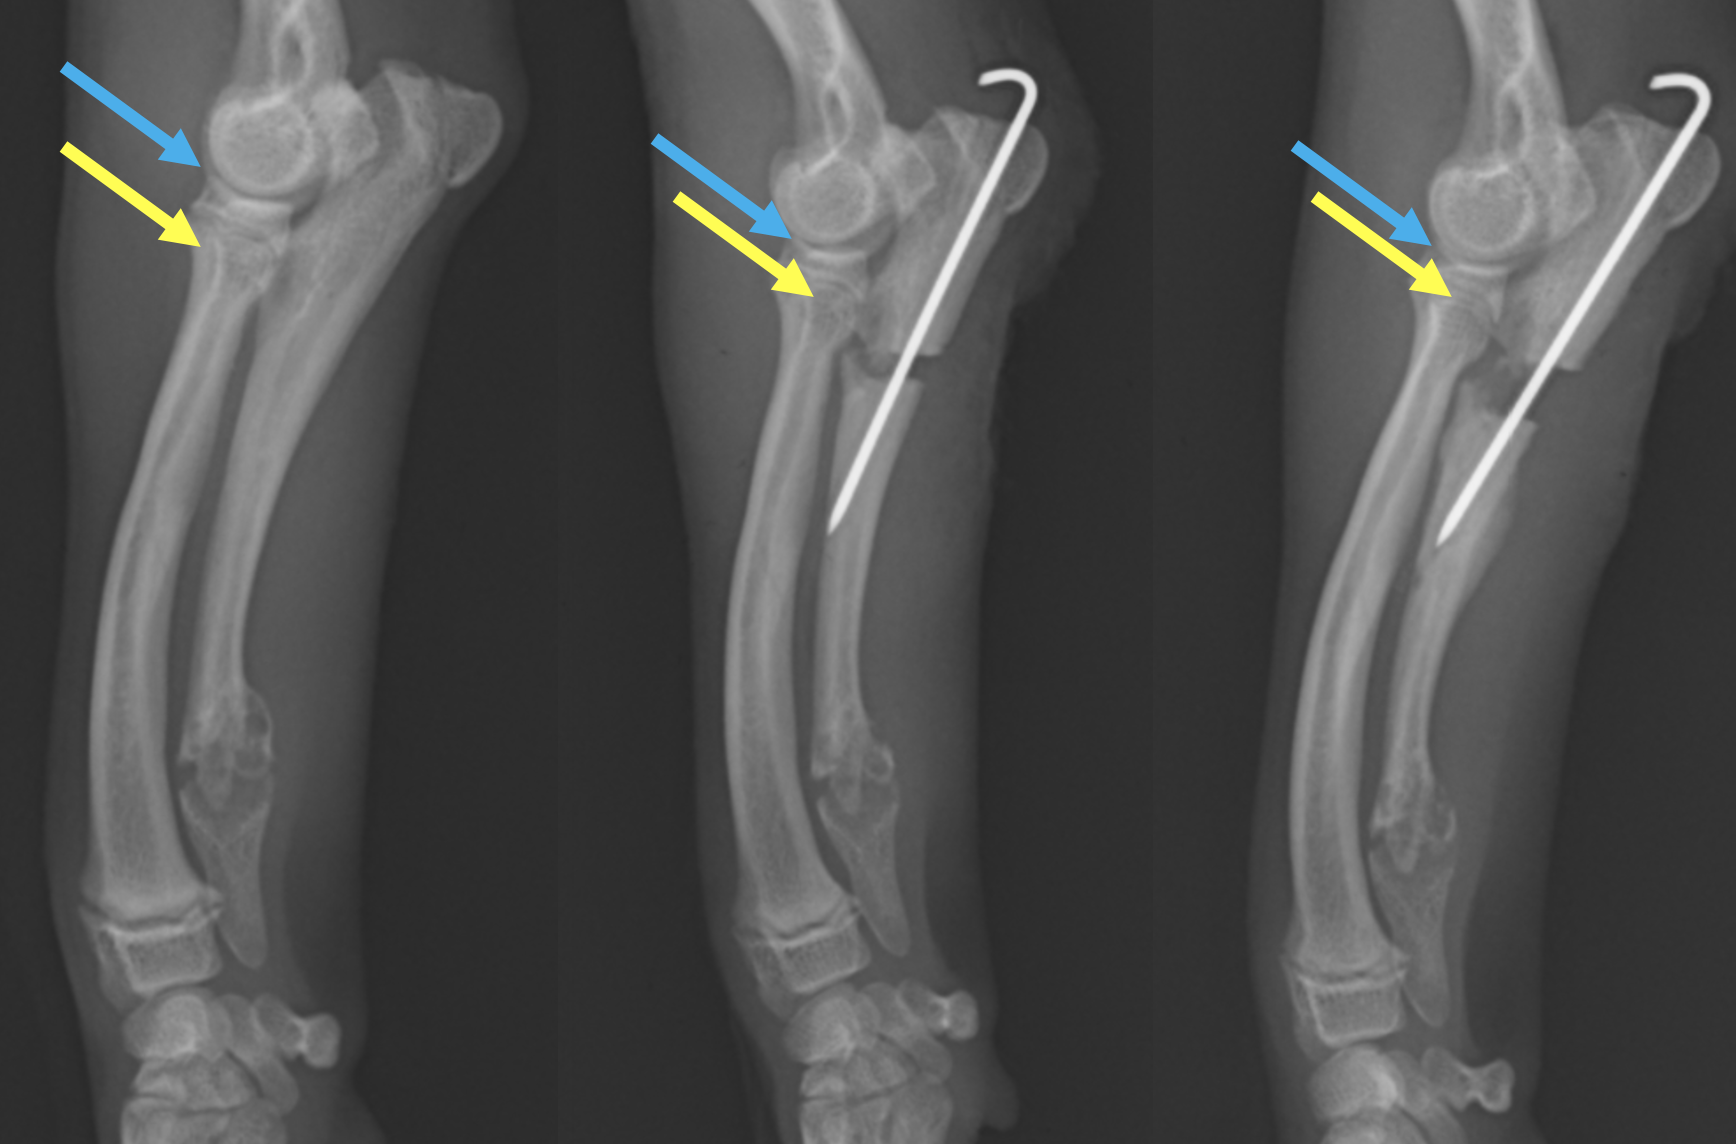

X線画像です。左が患肢で、右が正常肢です。2本ある骨のうち、左が橈骨、右が尺骨といいます。患肢の尺骨遠位成長板が少し黒っぽくなっています。よく見ると肘の尺骨がずれているのが分かります。

術後のレントゲンです。黄色が尺骨の関節部分、青色が上腕骨の骨を指していますが、一番左の術前ではその間隔が広いのが分かると思います。術後少しその間隔が短くなっており(真ん中)、術後2週間ではさらに短縮され、肘が正常に近づいているのが分かると思います。